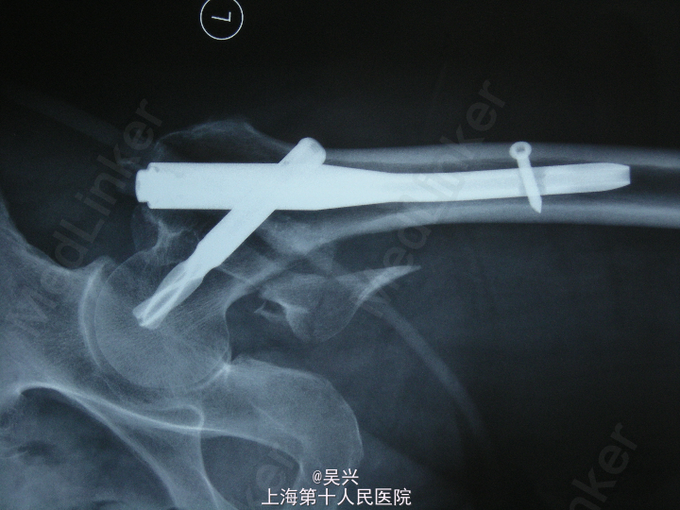

诊断:左股骨粗隆间骨折 处理:入院后予患肢皮肤牵引,完善术前准备,第3天行左股骨粗隆间骨折闭合复位、PFN-a内固定术。

随访:术后第1天,患者可坐起,翻身,术后3天可坐轮椅车外出,术后2月,骨折临床愈合可扶拐下地。 讨论:股骨粗隆间骨折是骨科常见的骨折之一,仅次于桡骨远端骨折。一般发生于高龄老年患者,如果不手术只能卧床、翻身困难,容易引起坠积性肺炎、褥疮等并发症危及生命。如果没有绝对禁忌症医生应该和患者家属充分沟通后积极手术,术前应纠正严重贫血。手术方式首选微创切口,PFN-a髓内固定,1、2型较稳定的也可选用DHS固定。术后可早期坐起翻身,防止卧床并发症。